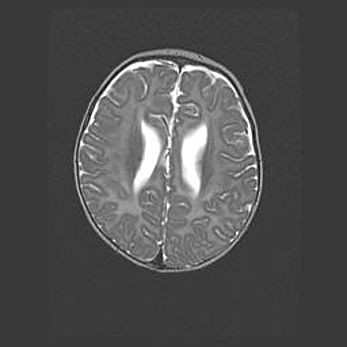

Лейкомаляция с кистозно-глиозной дегенерацией головного мозга.

Возраст: 2 месяца 25 дней

Вес: 6400 г

Окружность головы: 40 см

Срок гестации: 41 неделя

Лейкомаляцию относят к ишемически-гипоксическим повреждениям головного мозга, диагностируемым у новорожденных. При лейкомаляции в головном мозге обнаруживают очаги некроза, возникшие после тяжелой гипоксии и нарушения кровотока. В процессе морфогенеза очаги проходят три стадии: 1) развития некроза, 2) резорбции и 3) формирования глиозного рубца или кисты. Перивентрикулярная лейкомаляция (ПЛ) встречается примерно в 12% случаев среди новорожденных, обычно – у недоношенных детей, причем, частота ее зависит от массы, с которой младенец появился на свет. Наибольшее число малышей страдает лейкомаляцией, если масса при рождении 1500-2500 г.